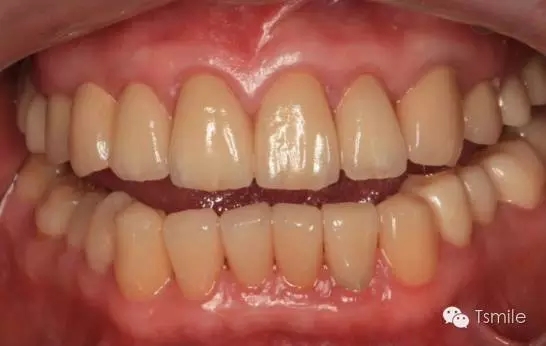

圖6:最終修復(fù)體完成